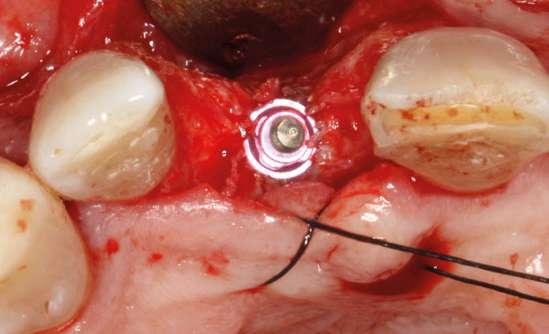

Colocamos el implante generándose una ligera expansión vestibular, como mostramos en las imágenes intraoperatorias, para posteriormente ser sobrecorregido con hueso autólogo obtenido del fresado, embebido en PRGF-endoret y lograr una mayor anchura vestíbulo-lingual en la zona de colocación del im-

plante, clave para lograr una mejor estética y además un mantenimiento de los tejidos periimplantarios a largo plazo. En la fase quirúrgica colocamos además el transepitelial unitario para la realización de la carga inmediata y la colcación de un provisional atornillado horas después de la cirugía (figuras 7-14).

Figuras 7 y 8. Perforación inicial y colocación del implante expandiendo la zona vestibular.

Figuras 9 y 10. Visión vestibular tras la inserción del implante y colocación del transepitelial unitario para comenzar la carga inmediata.

Figuras 11 y 12. Sobre-corrección vestibular y cierre primario de los tejidos con un monofilamento no reabsorbible alrededor de la tapa de protección del transepitelial.